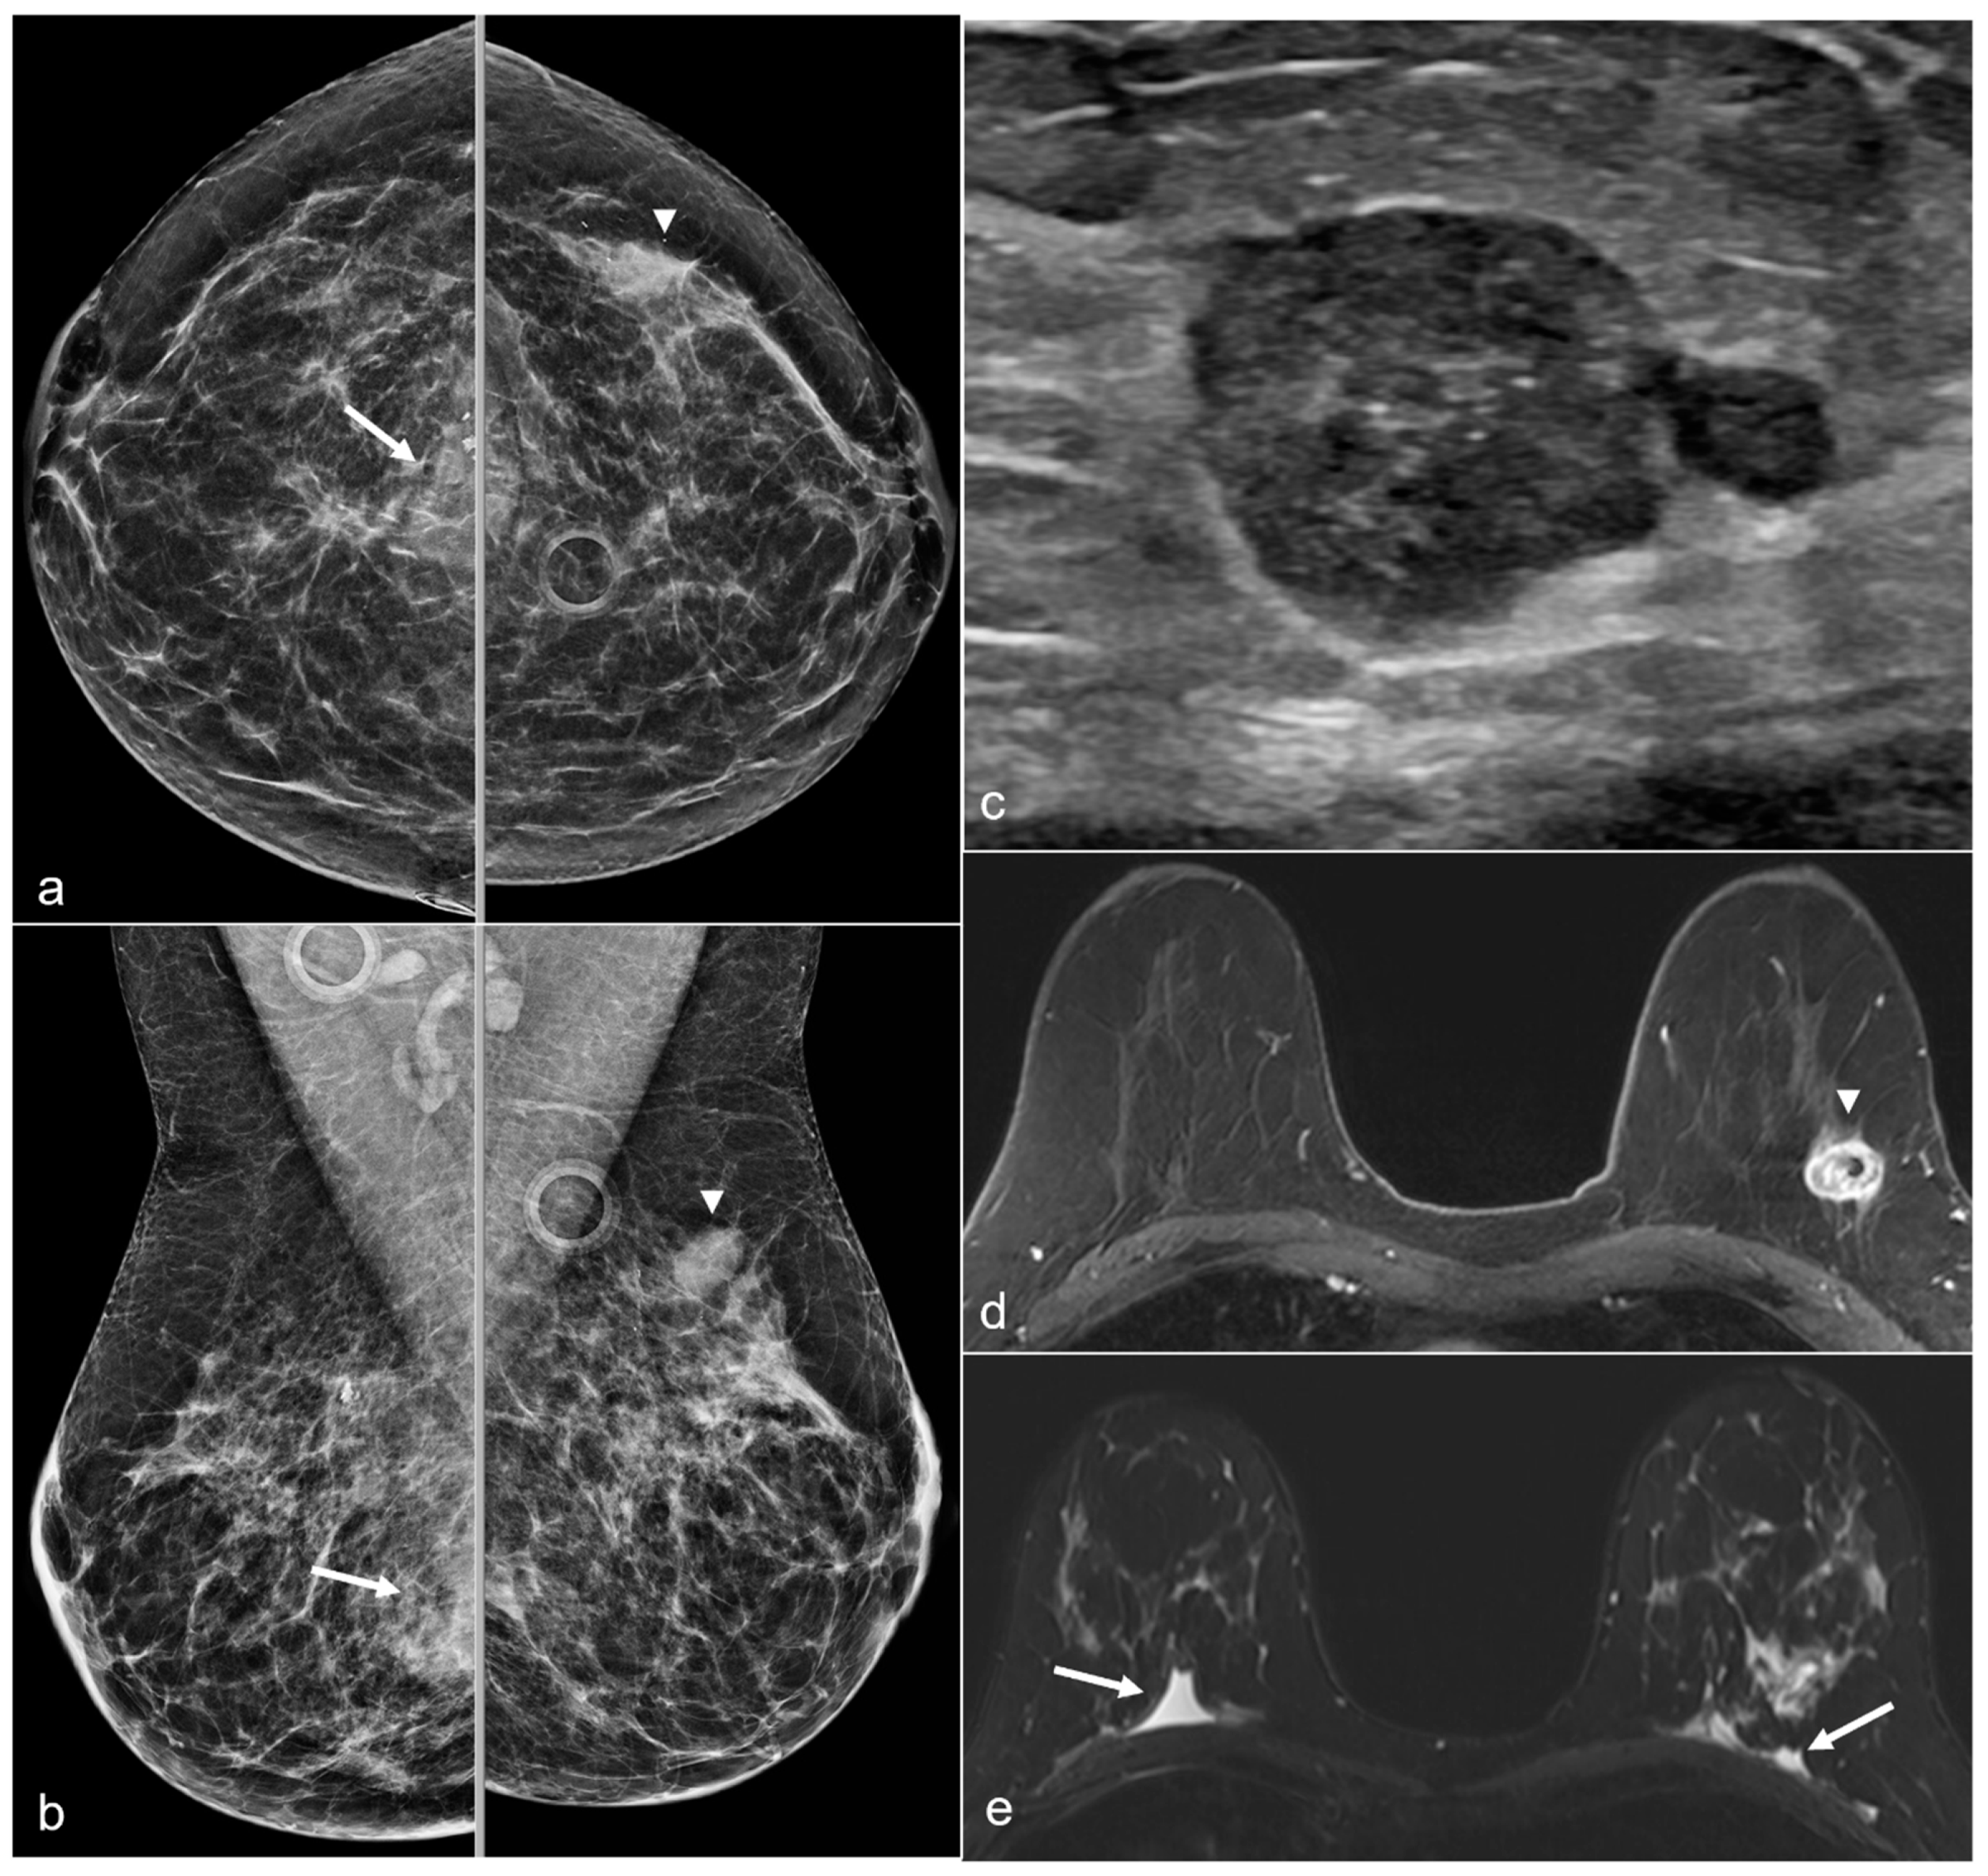

Figure 14. A 65-year-old woman with a history of a ruptured subglandular silicone implant. Screening mammogram (a) demonstrates very dense masses (arrows) in the left prepectoral region on the CC and the MLO views. Suspicious right breast calcifications (arrowhead) were biopsied with a biopsy clip seen in a hematoma in the right prepectoral region on the CC and MLO views. Pathology revealed ductal carcinoma in-situ. An additional biopsy was performed in the right breast for a small focal asymmetry (*) better seen on magnified CC view (b) and pathology demonstrated invasive ductal carcinoma. MRI demonstrates a T1 isointense peripherally enhancing silicone granuloma in the left breast prepectoral region ((c), arrows). In the right breast, a biopsy clip is seen within the biopsy cavity ((d), arrowhead). Anterior and inferior to this region (e), there is a linear non-mass enhancement. More anterior and medial to the non-mass enhancement, there is an enhancing mass (*), corresponding to the biopsy-proven invasive ductal carcinoma.